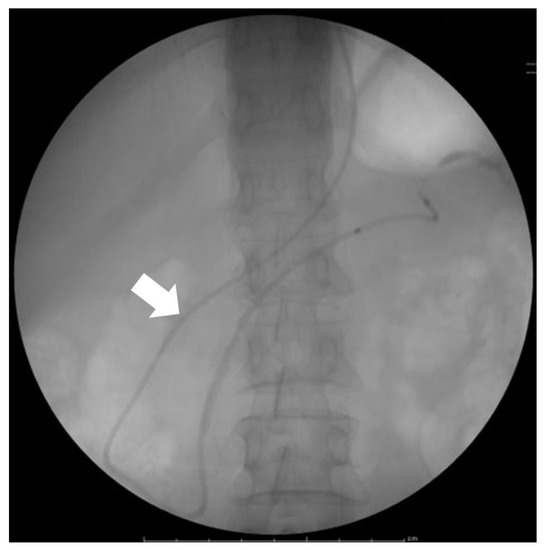

- Satoh, T.; Kikuyama, M.; Kawaguchi, S.; Kanemoto, H.; Muro, H.; Hanada, K. Acute Pancreatitis-Onset Carcinoma In Situ of the Pancreas with Focal Fat Replacement Diagnosed Using Serial Pancreatic-Juice Aspiration Cytologic Examination (SPACE). Clin. J. Gastroenterol. 2017, 10, 541–545. [Google Scholar] [CrossRef] [PubMed]